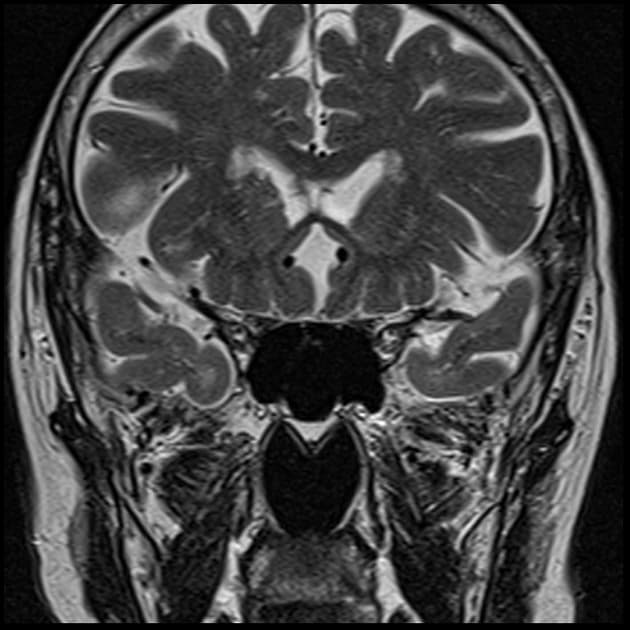

- Khối liên tục với cuống yên, làm giãn cuống này cả phía trên và phía dưới.

- Phù hợp với kiểu tăng quang đặc trưng và nằm trong cuống yên (infundibulum).

- Khối phù hợp với kiểu tăng quang đặc trưng và nằm trong cuống yên (infundibulum).

- Khối liên tục với cuống yên, làm giãn cuống cả phía trên và phía dưới.

- "Đặc điểm hình ảnh gồm khối u ranh giới rõ, tăng quang mạnh, liên tục với và làm giãn cuống yên."

U Pituicytoma là một loại khối u thần kinh đệm lành tính, phát triển chậm và hiếm gặp, xuất phát từ các tế bào pituicyte ở thùy sau tuyến yên hoặc cuống yên. Khối u thường biểu hiện như một tổn thương ranh giới rõ, tăng quang mạnh và liên tục với, đồng thời làm giãn cuống yên. Trên cộng hưởng từ (MRI), khối u thường có tín hiệu đẳng trên hình ảnh T1 và tăng quang đồng nhất sau khi tiêm thuốc cản quang. Việc không có dấu hiệu ác tính, không bệnh toàn thân và tổn thương ổn định dài hạn trên hình ảnh học làm tăng khả năng chẩn đoán u Pituicytoma, ngay cả khi chưa xác định bằng mô bệnh học. Các chẩn đoán phân biệt bao gồm u tuyến yên có liên quan đến cuống yên, u màng não và bệnh tổ chức bào Langerhans, những bệnh này có thể có hình ảnh tương tự. Tuy nhiên, vị trí đặc hiệu trong cuống yên và sự liên tục với cuống làm nghiêng về chẩn đoán u Pituicytoma. Điều trị thường mang tính theo dõi bảo tồn, đặc biệt ở bệnh nhân không có triệu chứng.